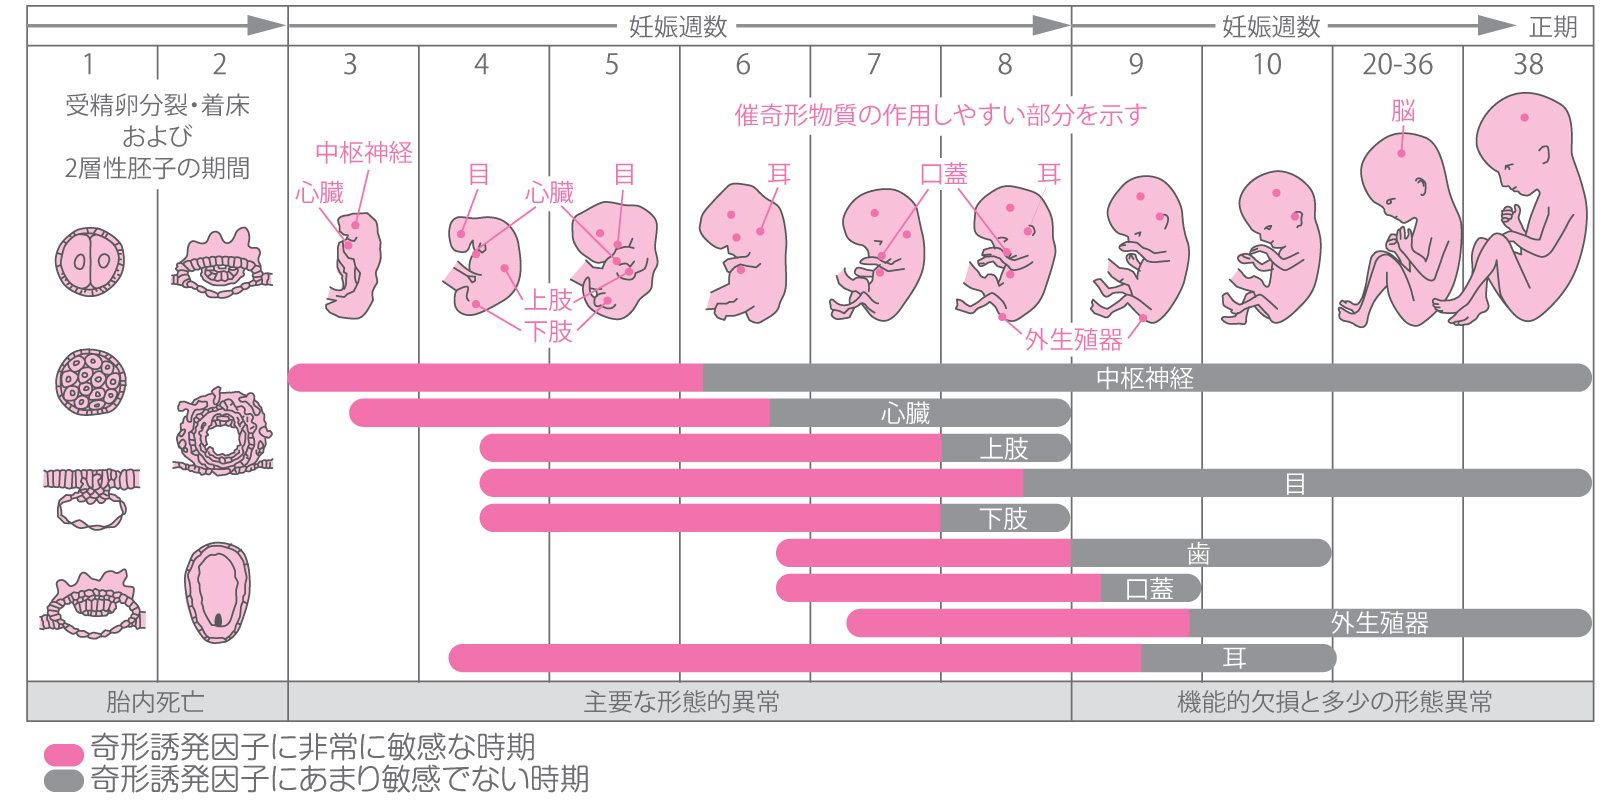

胎児は 5 週目あたりから脳の発達のプロセスを開始しますが、本当の楽しみが始まるのは、神経管が閉じて脳が 3 つの部分に分離する 6 週目か 7 週目になってからです。

生後 5 週目ごろ、赤ちゃんの脳、脊髄、心臓が発達し始めます。赤ちゃんの脳は中枢神経系の一部であり、脊髄もそこにあります。赤ちゃんの脳には考慮すべき重要な要素が 3 つあります。これらには次のものが含まれます。

ゲイザー氏によれば、4週間以内に神経板として知られる基本的な構造が発達し、これが神経系の前駆体であると考えられているという。 「このプレートは伸びて折り重なって神経管を形成します。神経管の頭側部分は脳になり、尾側部分は伸びて最終的には脊髄になります」と彼女は説明する。

神経管は成長を続けるが、6週目か7週目あたりで神経管が閉じ、頭側部分(原始脳とも呼ばれる)が前脳、中脳、後脳という3つの異なる部分に分離するとゲイザー氏は言う。

脊髄内でニューロンとシナプス(接続)が発達し始めるのもこの時期です。これらの初期の接続により、胎児は最初の動きを行うことができます。

ゲイザー氏は、妊娠第 2 期になると、脳が体の機能を制御し始めると述べています。これには、後脳、より具体的には小脳に由来する特定の動きが含まれます。

脳は妊娠第 1 学期の早い時期に形成され始め、出産まで続きます。妊娠中、胎児の脳の発達は、呼吸、蹴り、心拍などの特定の動作を担当します。